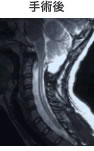

大後頭孔を拡大することで、小脳が正常な

位置に戻っています。脊髄空洞も縮小しています。